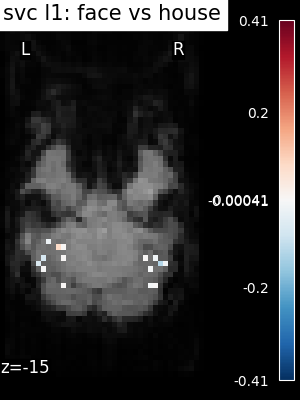

The corresponding weight maps (below) differ widely from one estimator to the other, although the prediction scores are fairly similar. In other terms, a well-performing estimator in terms of prediction error gives us little guarantee on the brain maps.

../_images/sphx_glr_plot_haxby_different_estimators_006.png ../_images/sphx_glr_plot_haxby_different_estimators_005.png ../_images/sphx_glr_plot_haxby_different_estimators_004.png ../_images/sphx_glr_plot_haxby_different_estimators_002.png ../_images/sphx_glr_plot_haxby_different_estimators_003.png